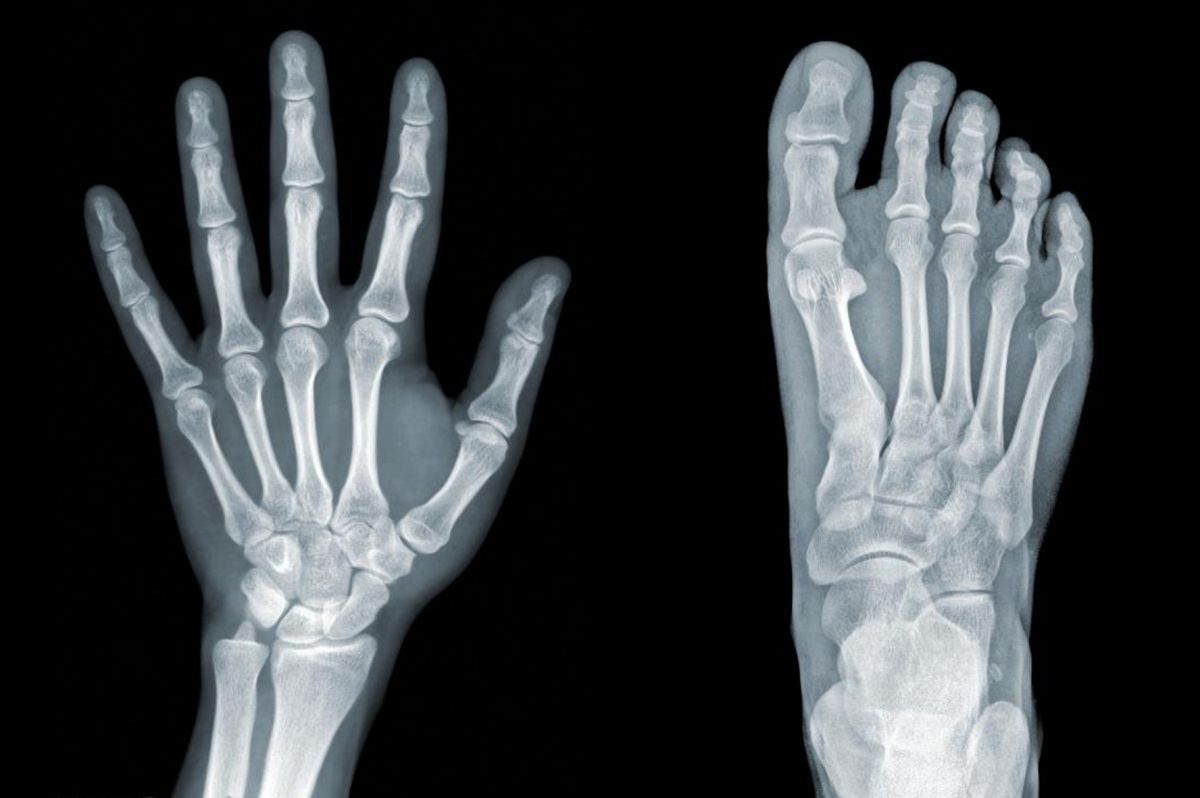

Jelenleg főként az űrkutatásban, illetve a vadászrepülők hőszigeteléséhez használják. A Debreceni Egyetem Szervetlen és Analitikai Kémiai Tanszékén azonban most azt kutatják, hogyan lehetne csontpótlásra vagy a fogásztatban is alkalmazni.